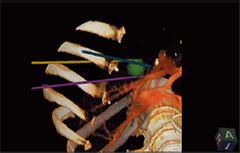

・3D Sim-Navigator

単数・複数本穿刺の際に,RVSでターゲットへのナビゲーションをしながら,穿刺ラインをシミュレーションします。

CTなどのボリュームデータから作成した3Dボディマークと,穿刺ラインとの直交断面を表示するC-planeを利用することにより,マークしたターゲットと穿刺ラインの位置関係をリアルタイムに三次元的に把握できます。

・E-field Simulator

RFA治療時の電極の配置から決定される電気的物理量(電場)をCTなどの画像上に表示します。複数本穿刺の際にもあらゆる電極配置に合わせて電場をシミュレーション可能なので,穿刺ライン検討の自由度が大幅に高まります。

これまでの手技を大幅に改善することが期待されます。